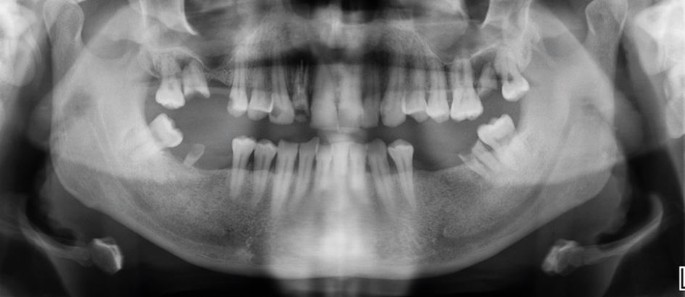

Orthopantomogram of the patient’s dentition

On examination, there was a loss of the nasal columella and saddle nose deformity. Intra-orally, there was complete erosion of the hard and soft palate and destruction of the nasal septum, with superimposed overgrowth of tissue and suppuration extending from the anterior hard palate posteriorly toward the oropharynx. The defect was surrounded with florid angiomatous tissue and bordered with crusted necrotic tissue (Fig. 5, Fig. 6). All remaining maxillary teeth were mobile (Fig. 7).